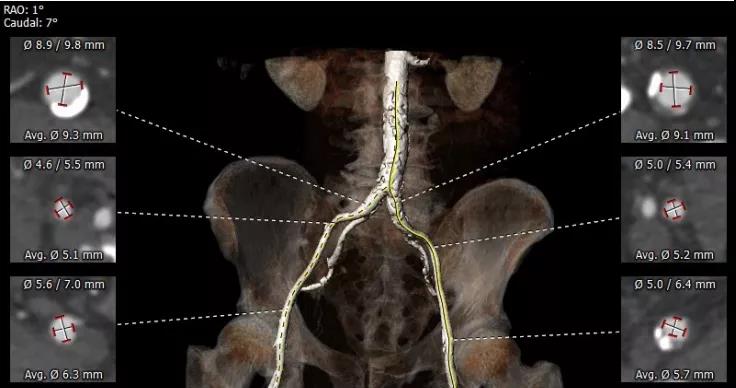

CT重建显示患者双侧髂动脉、股动脉、锁骨下动脉质量极差,多发钙化狭窄伴局部夹层,无法经股动脉和锁骨下动脉入路。而且患者重度肺气肿致心脏两侧受压,心尖被压缩在胸骨及肋弓骨性融合后方,亦无法经心尖入路。评估双侧颈动脉近端均有钙化斑块伴轻度狭窄,平均管径约6mm,左侧管径略大于右侧。颅内Willis环交通支通畅,可以耐受经单侧颈动脉介入手术。

经术前详尽影像学重建、评估及病例讨论,最终决定在脑氧监测下对患者实施经左侧颈总动脉TAVI手术。术中左侧颈总动脉多次预扩后顺利置入血管鞘至升主动脉,跨瓣成功后先以23#球囊预扩,再“0位”植入25# Renatus介入主动脉瓣。手术耗时约2小时,介入主动脉瓣植入位置理想,功能表现良好,主动脉瓣峰值流速及平均跨瓣压差分别降至1.75m/s和5mmHg,造影及TEE观察仅有轻微瓣周漏,无中央型反流。术后左颈总动脉造影无明显狭窄,手术全程脑氧饱和度正常,无传导阻滞、无冠脉异常。

颈动脉评估